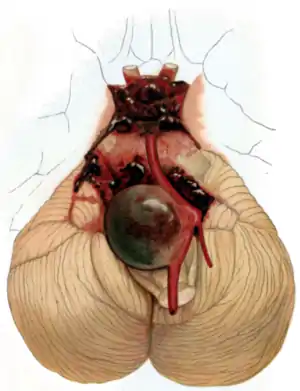

Surgical clipping

Aneurysms can be treated by clipping the base of the aneurysm with a specially-designed clip. Whilst this is typically carried out by craniotomy, a new endoscopic endonasal approach is being trialled.[30] Surgical clipping was introduced by Walter Dandy of the Johns Hopkins Hospital in 1937.[31] After clipping, a catheter angiogram or CTA can be performed to confirm complete clipping.[32]